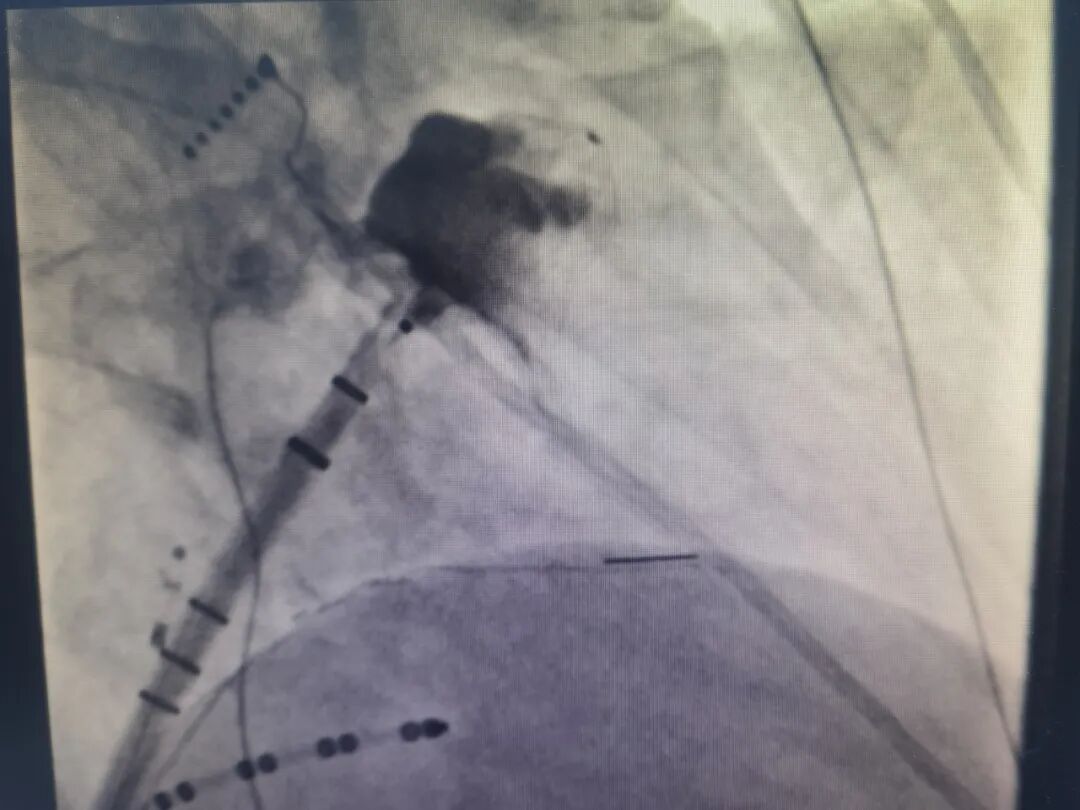

经多方打听,赵阿姨最终来到吴淞中心医院廖敏蕾主任医师的专家门诊就诊,廖主任高度重视,迅速邀请复旦大学附属中山医院心内科和吴淞中心医院心血管内科的专家进行会诊。经过深入讨论和全面评估,团队决定为赵阿姨实施“心房颤动射频消融术+左心耳封堵”一站式手术。

在中山医院专家的悉心指导下,吴淞中心医院心血管内科主任施鸿毓与主治医师张振洲密切配合、精准定位,在封堵伞后下缘外侧成功完成了房间隔穿刺。

由于穿刺空间极为有限,他们不得不打破常规(通常情况下,射频消融手术需保留两根鞘管配合操作),仅使用单根鞘管在左心房内操作,这无疑是对手术技巧和团队协作能力的巨大考验。但凭借着过硬的专业素养和丰富的临床经验,施主任团队顺利完成了射频消融术和左心耳封堵术,为赵阿姨的心脏健康筑起了一道坚固的防线。

成功完成射频消融术和左心耳封堵术